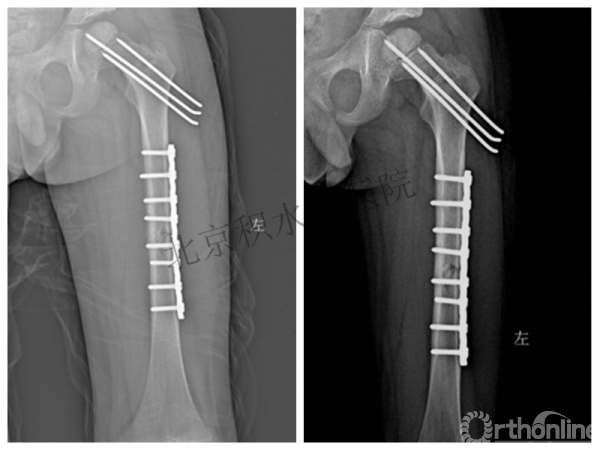

又过了4年!时间来到2015年

一年以后顺利愈合,实则危机四伏

数月后再骨折!牵引!

髋人字支具

外固定架术后一年

整整11年!是否治疗终结?

病人的付出?医生当反思!